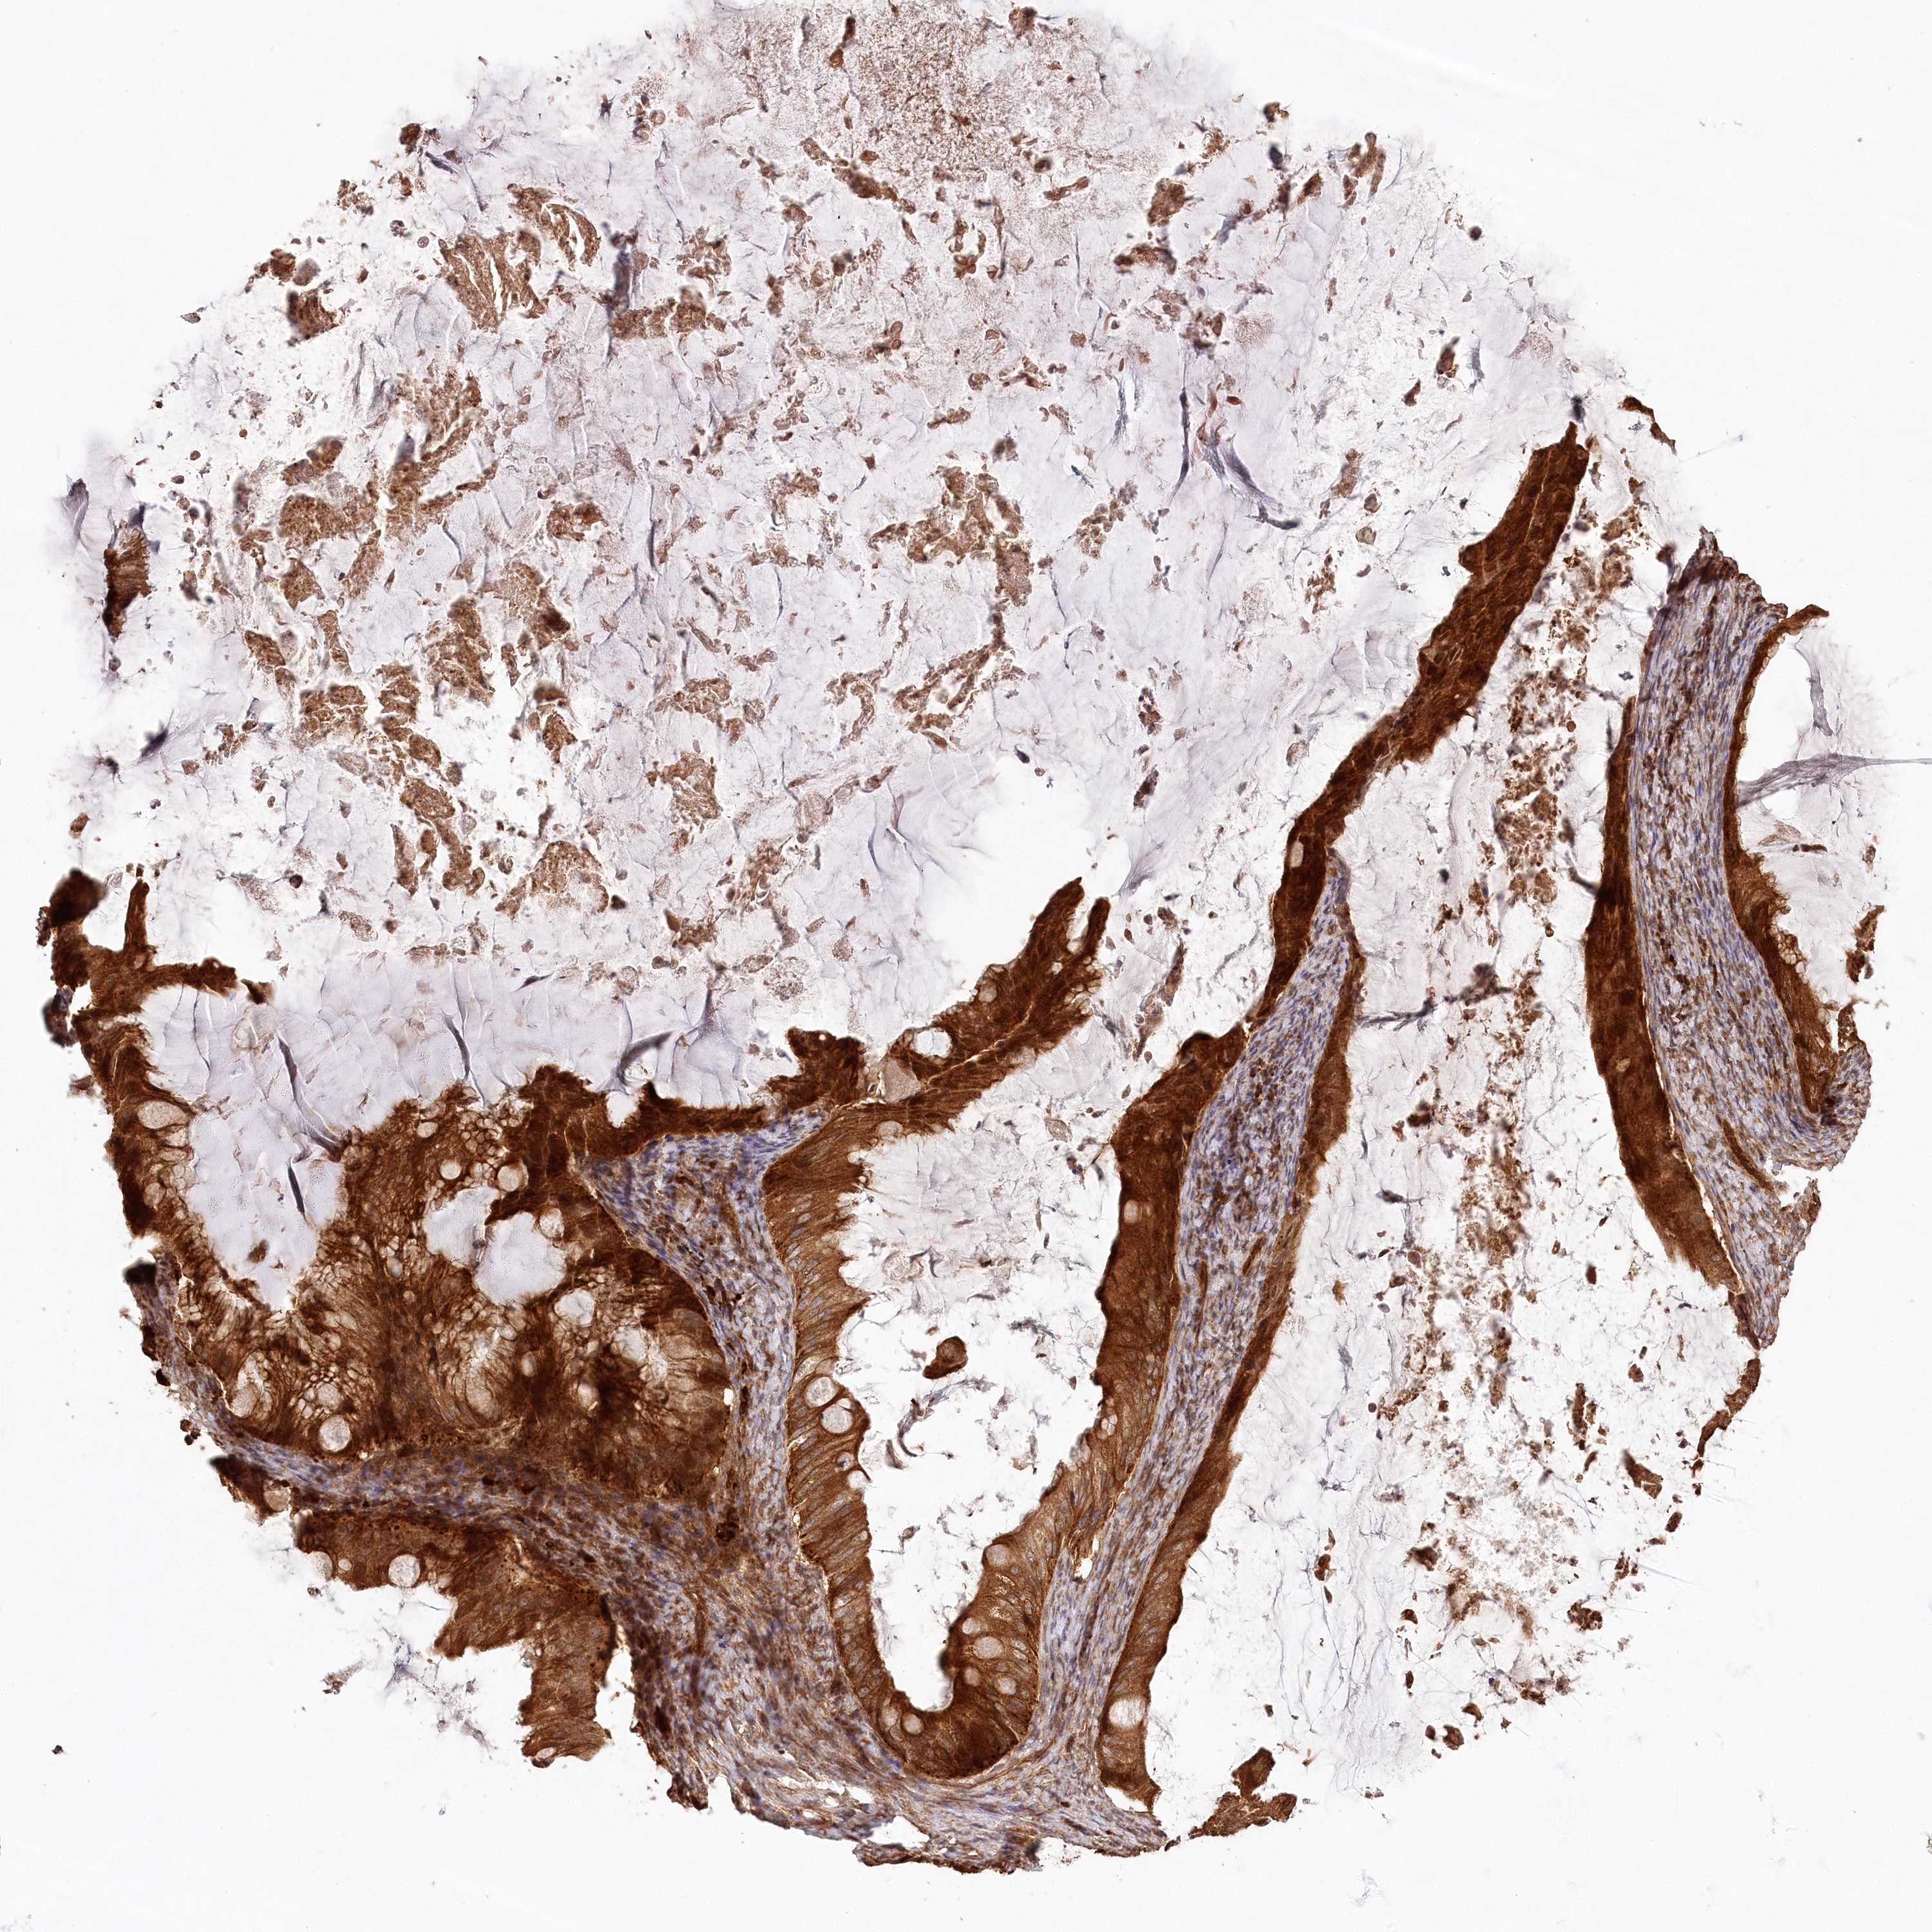

OVARIAN CANCER - Protein expressioni

A mouse-over function shows sample information and annotation data. Click on an image to view it in a full screen mode. Samples can be filtered based on level of antibody staining by selecting one or several of the following categories: high, medium, low and not detected. The assay and annotation is described here.

Note that samples used for immunohistochemistry by the Human Protein Atlas do not correspond to samples in the TCGA dataset.

Antibody stainingi

Antibody staining in the annotated cell types in the current human tissue is reported as not detected, low, medium, or high, based on conventional immunohistochemistry profiling in selected tissues. This score is based on the combination of the staining intensity and fraction of stained cells.

Each image is clickable and will lead to virtual microscopy that enables deeper exploration of all samples and also displays staining intensity scores, fraction scores and subcellular localization as well as patient and tissue information for each sample.

Antibody HPA032060

Antibody CAB034116

Staining

High

Medium

Low

Not detected

Intensity

Strong

Moderate

Weak

Negative

Quantity

>75%

75%-25%

<25%

None

Location

Nuclear

Cytoplasmic/membranous

Cytoplasmic/membranous,nuclear

Cystadenocarcinoma, serous, NOS

Carcinoma, endometroid

Cystadenocarcinoma, mucinous, NOS

Carcinoma, NOS